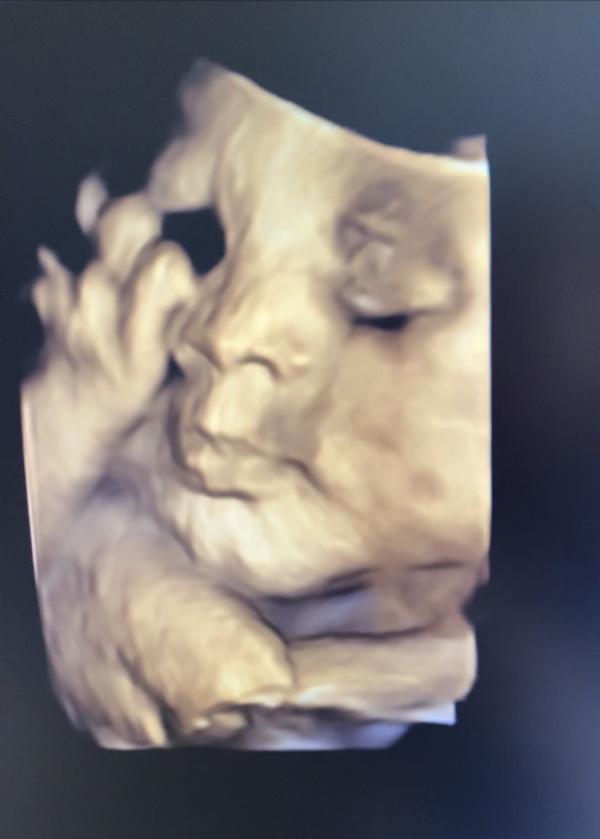

Вчера была на 3 скрининге.

Малыш улыбался, видимо будет весельчак🙃

А ещё у него похоже будут ямочки на щёчках, как у меня😊

Но по своему ребёнку узнала нос мужа, свой подбородок и ямочки😊